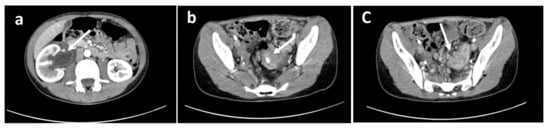

At medical history, he reported chronic constipation with occasional colic abdominal pain, two episodes of rectal bleeding two years and two months before, hyporexia, and weight loss of about two kilos (10% of his weight) in the last two months. No vomiting episodes were reported. Previous laboratory tests excluded food allergies and celiac disease. At physical examination, he was pale, cachectic, and suffering from pain in the right lumbar region. Abdominal ultrasonography showed right hydroureteronephrosis. A Computed Tomography (CT) scan confirmed hydroureteronephrosis with right ureter incorporated inside a retroperitoneal 14 × 7 × 4 cm unresectable nodal mass infiltrating multiple small bowel segments and a concentric thickening of the sigmoid walls, extended by about 6 cm, with the presence of centimetric calcification (Figure 1).

Figure 1. Computed Tomography images showing (a) right globular kidney site of hydro-ureteronephrosis; the ureter appeared markedly dilated up to the iliac tract where it was incorporated by a solid tissue with post-contrast enhancement of likely lymph node nature. This tissue extended from the right renal pelvis into the peri-ureteral adipose tissue (overall extension of about 14 × 7 × 4 cm). (b) a concentric thickening of the walls of the sigmoid was also evident, extended for about 6 cm, with the presence of centimetric calcification in the context. (c) multiple lymph nodes with rounded morphology, partially confluent were present in the perisigmoid meso with a maximum size of about 16 mm.